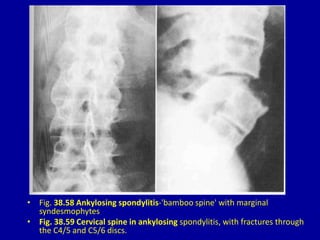

• Fig. 38.58 Ankylosing spondylitis-'bamboo spine' with marginal

syndesmophytes

• Fig. 38.59 Cervical spine in ankylosing spondylitis, with fractures through

the C4/5 and C5/6 discs.

• Fig. 38.58Ankylosing spondylitis-'bamboo spine' with marginal syndesmophytes • Fig. 38.59 Cervical spine in ankylosing spondylitis, with fractures through the C4/5 and C5/6 discs.